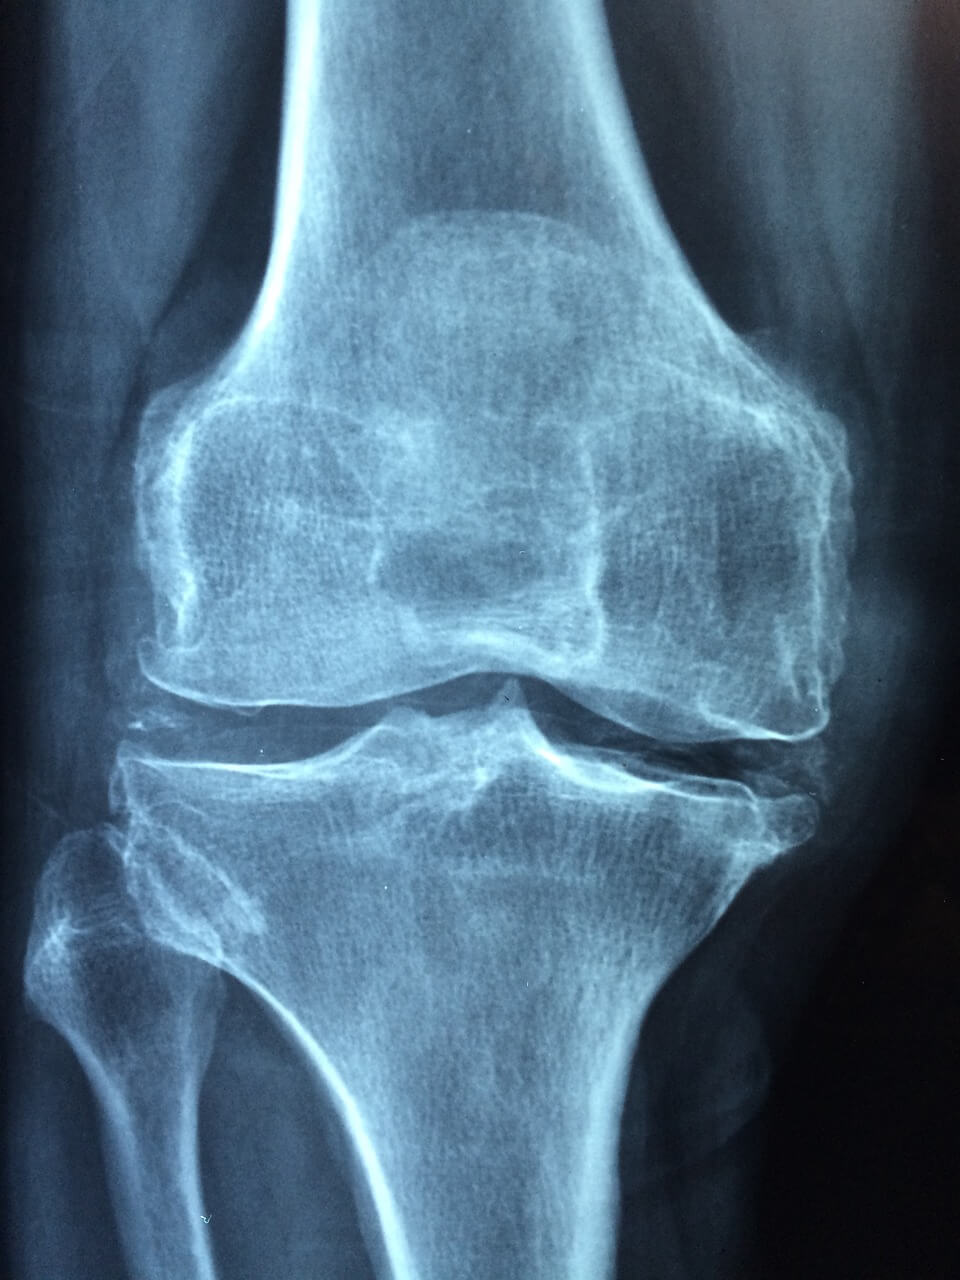

세 번째는 관절증상으로 손가락 류마티스 관절염 초기증상이 여기에 해당합니다. 초기 류마티스 관절염의 중요한 특징은 침범된 관절의 통증과 종창입니다. 진단에 중요한 증상은 손에서 많이 발견되는데 류마티스 관절염은 손가락의 중간마디와 손바닥 부위를 잘 침범하고, 손가락 끝마디의 관절은 잘 침범하지 않는 경향이 있습니다. 침범된 관절은 만지면 아프고 움직임이 제한되며, 손바닥의 홍반이 동반되기도 합니다. 또한 손목을 뒤로 굽히는 데 장애가 생기고 손가락을 굽히는 데에도 장애가 생깁니다. 주먹을 꽉 쥘 수 없는 경우도 많으며, 이러한 증상이 있는 경우는 필히 병원을 방문하여 치료를 받으시기 바랍니다. 이후 증세는 무릎 등 큰 관절로 어어질 수 있습니다. 80% 이상의 환자가 무릎 류마티스 관절염으로 고생한다고 하니 참고해 주세요.